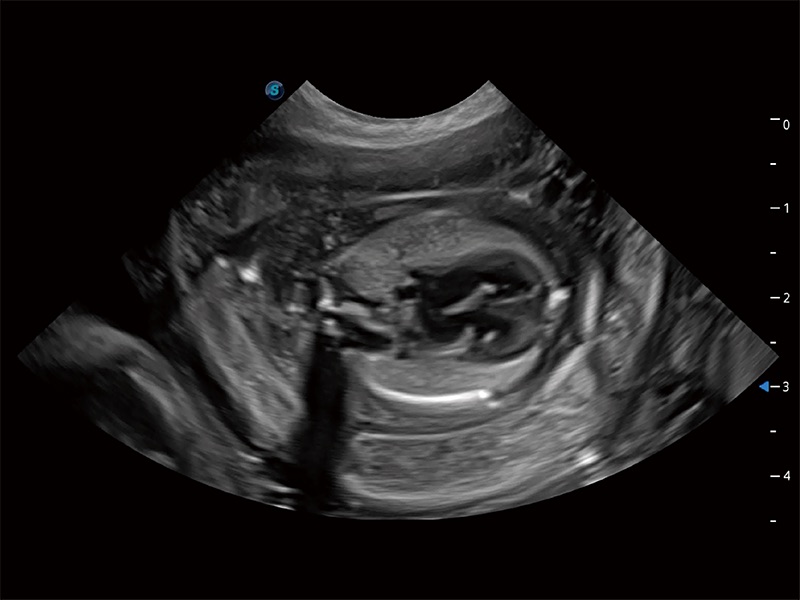

高性能和先进的临床应用工具可以为动物医生提供临床信心。ProPet 80 搭载了先进的腹部和浅表应用工具,帮助医生在日常临床实践中发挥前所未有的作用。

ProPet 80 专为动物医生设计,对不同的动物体型和生理结构作出了针对性的优化。通过动物影像专用软件,可满足个性化的应用需求,帮助动物医生获得更精确的诊断数据。